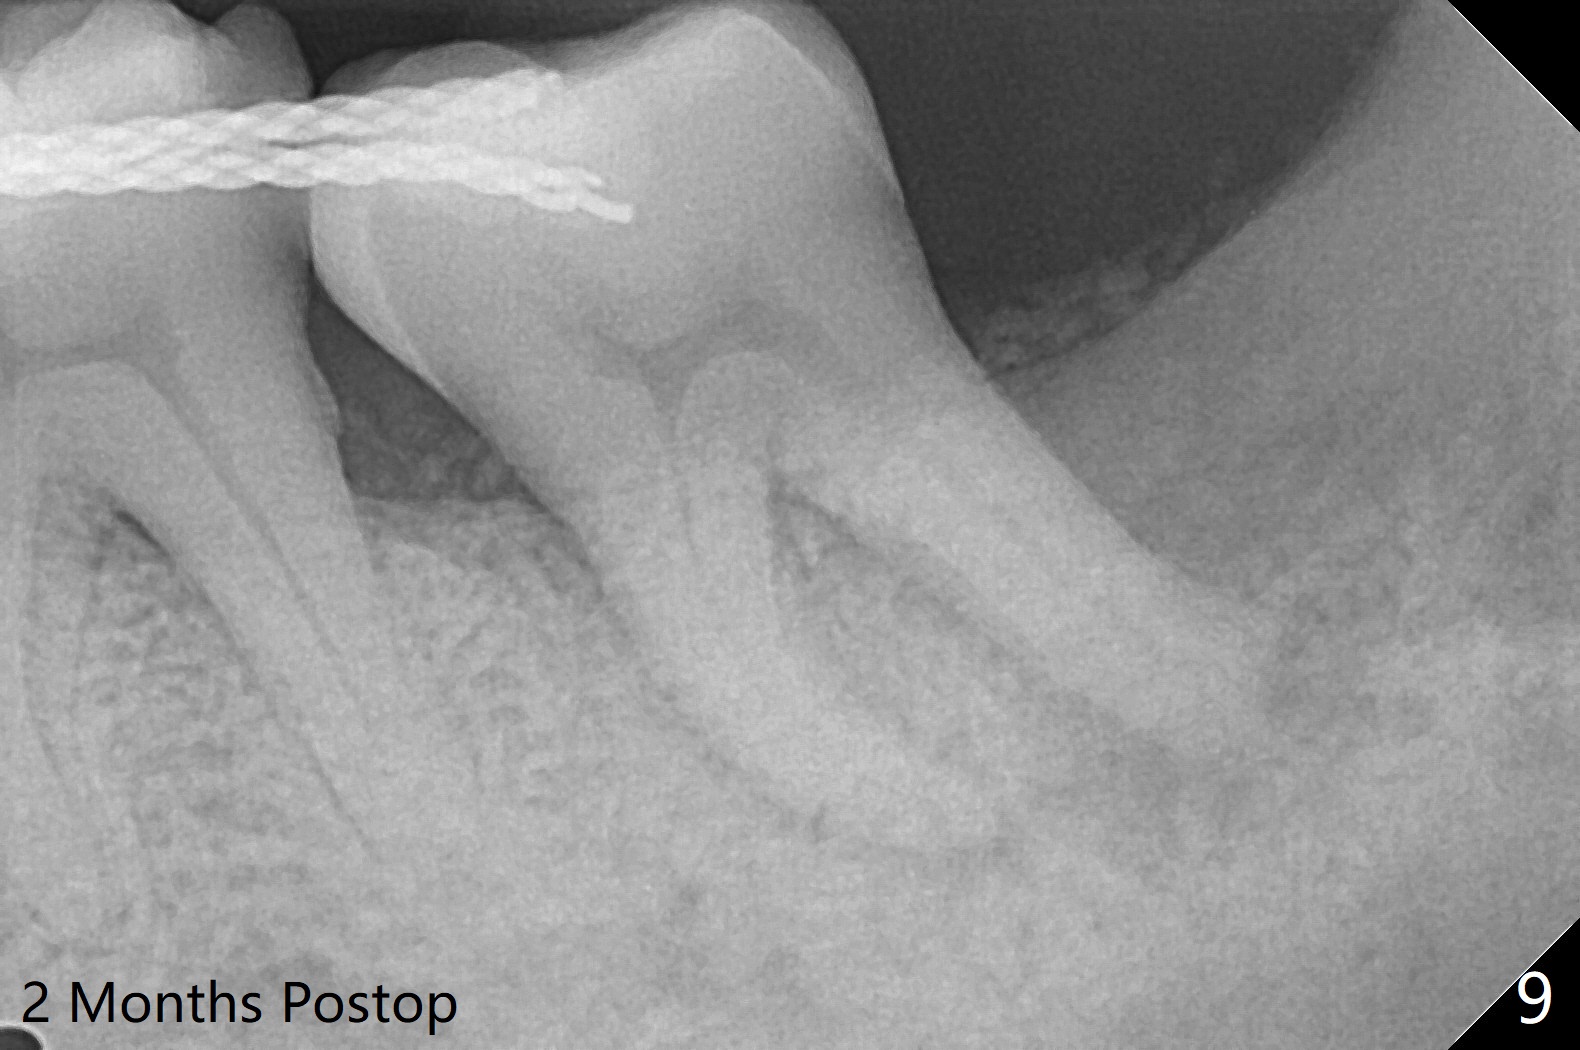

65岁女,南方人(广州),主诉左下肿胀,8舌侧粘膜穿孔(图一(舌侧观):<),初步问诊,回答:“全身没问题”,详细问诊:骨质疏松,静脉注射Reclast两年,准备拔除使用PRF修复缺损,全景片显示7远中骨质吸收严重(图二),因此8拔出后,牙槽窝塞入胶原塞(图五:C),将粘性骨粉放置7近中,远中(图五:白*)以及颊侧(黑*),把一片PRF膜覆盖骨粉(7颊侧,8牙槽窝口),另外一片放置于8舌侧穿孔(图四:箭头)颊侧,促进愈合,然后使用4-0 PGA缝合(图三(颊侧观),图四(舌侧观))。术后5天用钢丝(图六:*)和树脂固定松动牙,并且降低咬合。舌侧穿孔正在愈合(图七:>)。虽然术后三周智齿伤口裂开,但是没有症状,病人满意第二磨牙不再松动(图八),开始深洗。下次复诊拍摄根尖片观察骨质愈合。术后二个月第二磨牙远中没有骨质再生(图九),临床上远中牙根暴露。